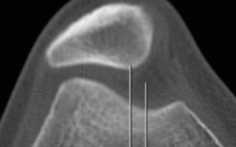

TA-GT

C + E (condyles + TTA)

C

Condyles (Arche romaine)